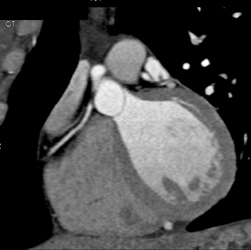

Diagnosis

Soft Plaque LAD